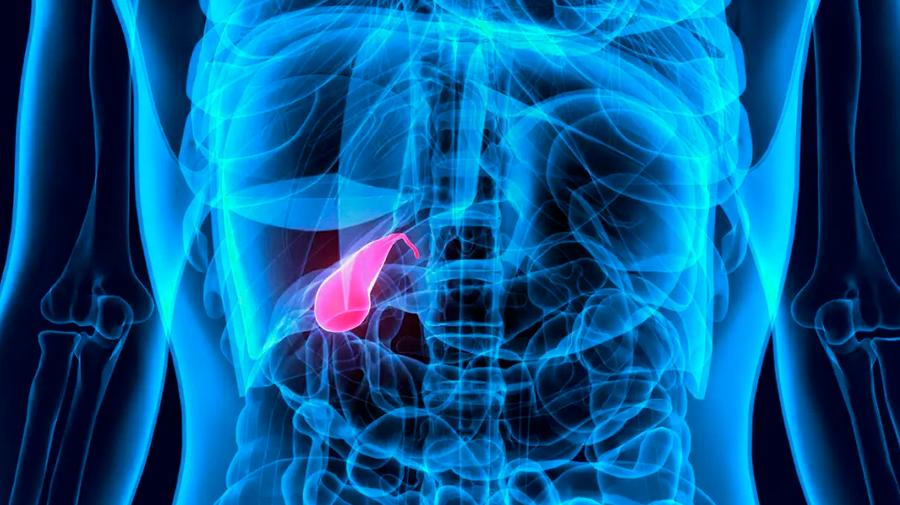

- Λαπαροσκοπική χολοκυστεκτομή

- Λαπαροσκοπική χολοκυστεκτομή

Ο Γενικός Χειρουργός Λιάγκος Γεώργιος MD PhD εκτελεί τις επεμβάσεις Λαπαροσκοπικά, Ενδοσκοπικά, Ανοιχτά Ελάχιστα Επεμβατικά και με Laser. Η θεραπεία εξατομικεύεται σε κάθε ασθενή ανάλογα με τις ανάγκες του. Αναλαμβάνει περιπτώσεις όπως κήλες και κοιλιοκήλες (αντιμετώπιση βουβωνοκήλης, αντιμετώπιση ομφαλοκήλης, θεραπεία επιγαστρικής κήλης, κήλη των αθλητών (Σύνδρομο κοιλιακών προσαγωγών), αντιμετώπιση μετεγχειρητικής κήλης, θεραπεία Μηροκήλης), πέτρες στη χοληδόχο κύστη, λαπαροσκοπική χολοκυστεκτομή, αντιμετώπιση Κύστη Κόκκυγος με λέιζερ (laser), παθήσεις πρωκτού, χειρουργική laser σύγχρονων κυκλικών ινών (αιμορροΐδες αντιμετώπιση, θεραπεία αιμορροϊδων με laser (LHP), αφαίρεση αιμορροΐδων με υπερήχους (HALL-RAR), χωρίς Χειρουργείο με ελαστικούς δακτυλίους (Τεχνική BARON-RBL), θεραπεία ραγάδας πρωκτού (Ραγάδα δακτυλίου), θεραπεία περιεδρικού συριγγίου, θεραπεία περιεδρικού αποστήματος, κονδυλώματα πρωκτού Θεραπεία, δερματικό ράκος (Skin tag) εκτομή, αντιμετώπιση Kνησμού, καρκίνος πρωκτού θεραπεία), παθήσεις Δέρματος, χειρουργική με laser CO2, αφαίρεση μορφωμάτων δέρματος - βιοψίες, αφαίρεση ελιάς (Σπίλου), σμηγματογόνος κύστης θεραπεία, αφαίρεση λιπώματος, είσφρυση όνυχος χειρουργείο, καρκίνος δέρματος θεραπεία, οξεία σκωληκοειδίτιδα, παθήσεις Λεπτού και Παχέος Εντέρου, ειλεός λεπτού εντέρου, εκκολπωμάτωση (Εκκολπωματίτιδα) σιγμοειδούς, καρκίνος παχέος εντέου, κολοστομίες, port χημειοθεραπείας κ.α.

Ο Γενικός Χειρουργός Λιάγκος Γεώργιος MD PhD εκτελεί τις επεμβάσεις Λαπαροσκοπικά, Ενδοσκοπικά, Ανοιχτά Ελάχιστα Επεμβατικά και με Laser. Η θεραπεία εξατομικεύεται σε κάθε ασθενή ανάλογα με τις ανάγκες του. Αναλαμβάνει περιπτώσεις όπως κήλες και κοιλιοκήλες (αντιμετώπιση βουβωνοκήλης, αντιμετώπιση ομφαλοκήλης, θεραπεία επιγαστρικής κήλης, κήλη των αθλητών (Σύνδρομο κοιλιακών προσαγωγών), αντιμετώπιση μετεγχειρητικής κήλης, θεραπεία Μηροκήλης), πέτρες στη χοληδόχο κύστη, λαπαροσκοπική χολοκυστεκτομή, αντιμετώπιση Κύστη Κόκκυγος με λέιζερ (laser), παθήσεις πρωκτού, χειρουργική laser σύγχρονων κυκλικών ινών (αιμορροΐδες αντιμετώπιση, θεραπεία αιμορροϊδων με laser (LHP), αφαίρεση αιμορροΐδων με υπερήχους (HALL-RAR), χωρίς Χειρουργείο με ελαστικούς δακτυλίους (Τεχνική BARON-RBL), θεραπεία ραγάδας πρωκτού (Ραγάδα δακτυλίου), θεραπεία περιεδρικού συριγγίου, θεραπεία περιεδρικού αποστήματος, κονδυλώματα πρωκτού Θεραπεία, δερματικό ράκος (Skin tag) εκτομή, αντιμετώπιση Kνησμού, καρκίνος πρωκτού θεραπεία), παθήσεις Δέρματος, χειρουργική με laser CO2, αφαίρεση μορφωμάτων δέρματος - βιοψίες, αφαίρεση ελιάς (Σπίλου), σμηγματογόνος κύστης θεραπεία, αφαίρεση λιπώματος, είσφρυση όνυχος χειρουργείο, καρκίνος δέρματος θεραπεία, οξεία σκωληκοειδίτιδα, παθήσεις Λεπτού και Παχέος Εντέρου, ειλεός λεπτού εντέρου, εκκολπωμάτωση (Εκκολπωματίτιδα) σιγμοειδούς, καρκίνος παχέος εντέου, κολοστομίες, port χημειοθεραπείας κ.α.